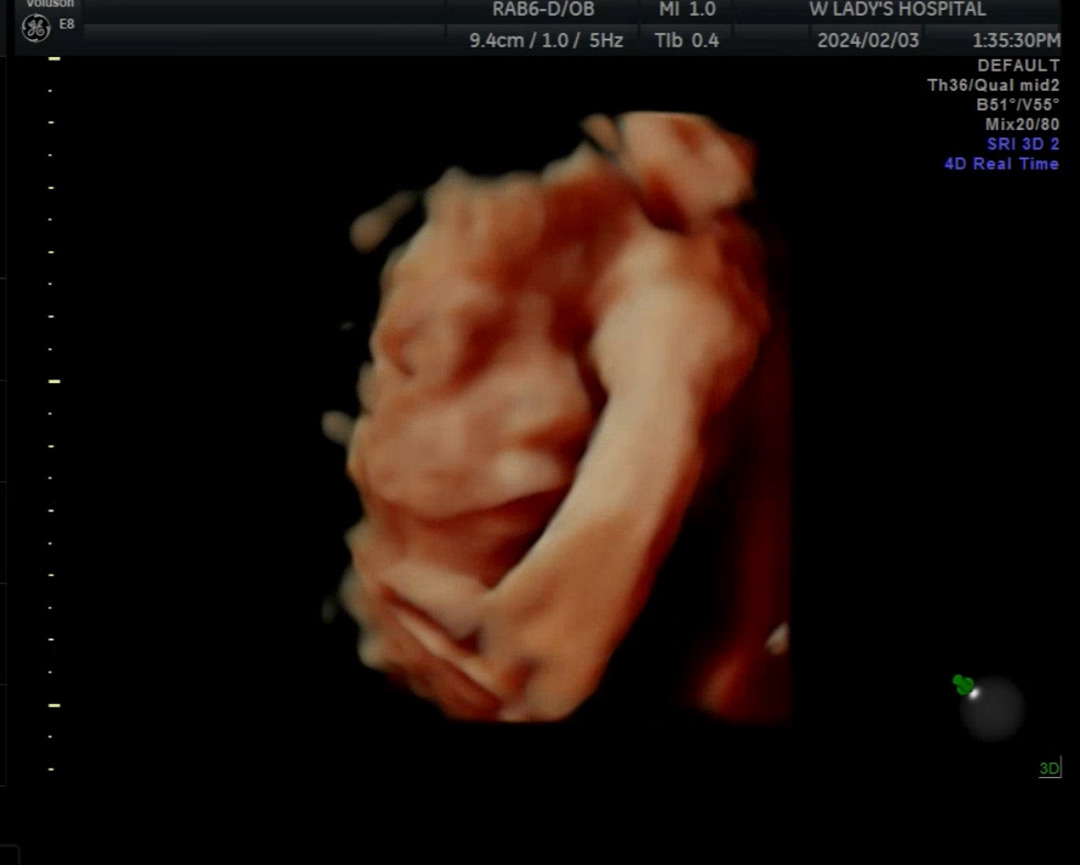

25주차에 본 우리용용이 입체에용 ㅎㅎ 언제나 손을 얼굴에 올리고 있는 우리아가 ㅎㅎ 이정도면 그래도 눈코입은 잘 본거 같은데 어떤가요?? 벌써부터 도치맘 확정이네요ㅋㅋㅋ

튼튼한 팔ㅎㅎㅎ 얼굴 잘보여서 부럽고 귀엽네요ㅎㅎㅎ